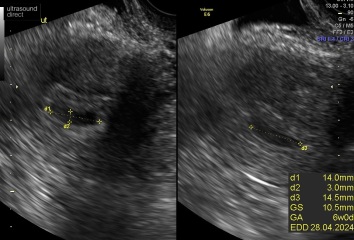

just for anyone who reads this thread, i went to EPU today for a scan, measured 12 week and saw heartbeat and “baby” who is a little blob at the moment☺️ not sure what happened at my early scan. Maybe i was too early or equipment wasnt the same. Learnt my lesson to be patient from now on

Thank you everyone for your comments and sorry for your loss hopeful mum.

Oop mean measured 6 week! Not 12! Getting ahead of myself😂